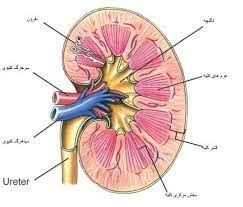

قیمت: 29٬500 تومان - دسته بندی فایل: پاورپوینتاسلاید آموزشی با عنوان مروری برآناتومی و فیزیولوژی کلیه

تعداد صفحه:14 صفحه دسته بندی:پاورپوینت فروش ویژه و محدود این پاورپوینت حرفه ای و درجه یک با تخفبف استثنایی فقط29500هزارتومان